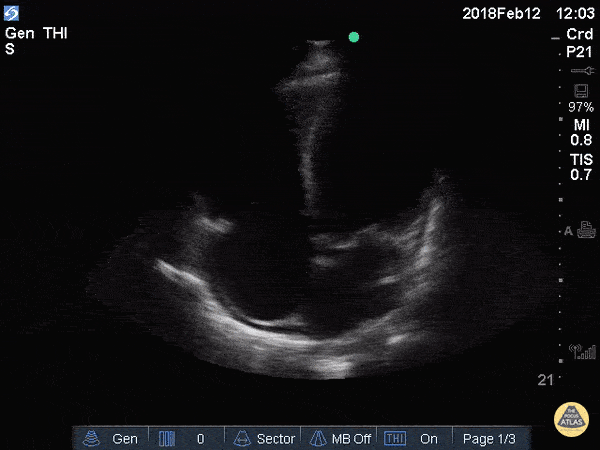

A 74-year-old with ischemic cardiomyopathy, HTN, and diabetes presents with 5 days of worsening exertional dyspnea, orthopnea, fatigue, and reduced exercise tolerance, but denies active chest pain. Vitals: T 36.7°C, HR 112, BP 94/62, RR 24, SpO₂ 92% on room air. Exam: bibasal crackles, S3, 2+ bilateral pitting edema. A parasternal long-axis clip is shown. Please describe the findings seen in this scan. What is the diagnosis?

Findings: Fractional shortening < 30%, EPSS > 1, grossly depressed LV systolic function

Diagnosis: Acute decompensated heart failure with reduced EF